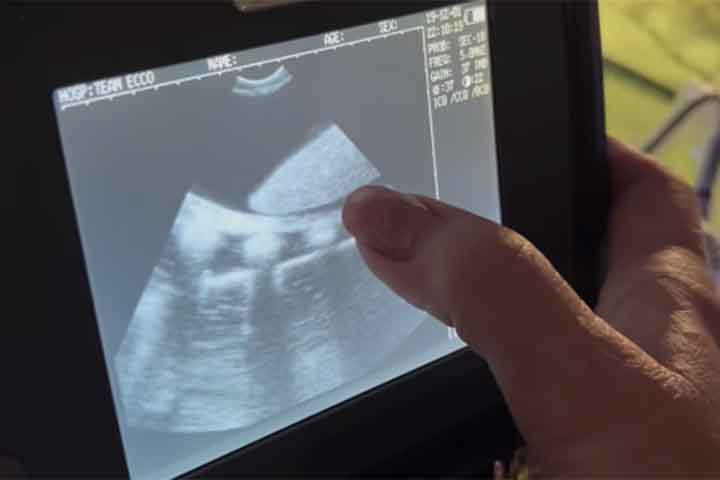

Independente: Arraia ‘engravida’ sem ter contato com macho